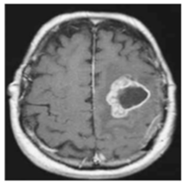

| No Tumor | Glioma Tumor | Meningioma Tumor | Pituitary Tumor | |

| Brain MRI Images |  ![]()  |  ![]()  |  ![]()  |  ![]()  |